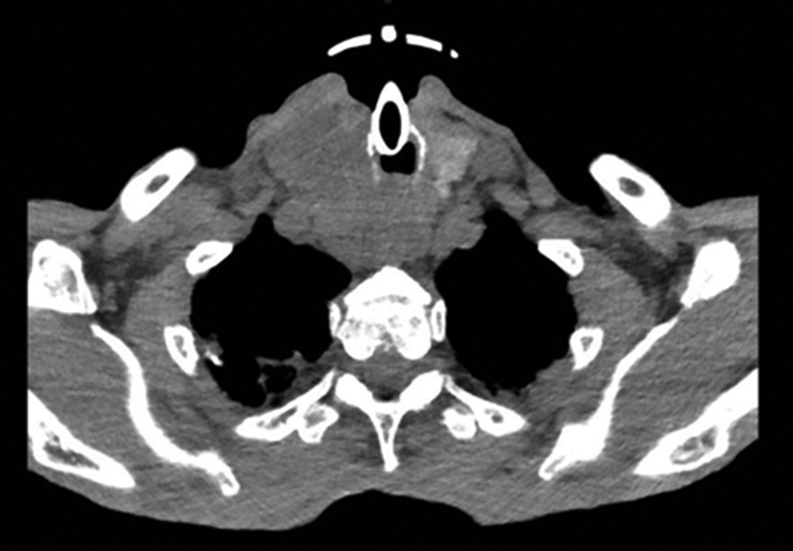

Summary: We report the case of an 88-year-old man hospitalized for COVID-19 with persistently very high procalcitonin (proCt) levels despite infection resolution. Since proCt is an adjunct tumor marker in the diagnosis of medullary thyroid carcinoma (MTC), serum calcitonin (Ct) was also measured showing very high levels. Computed tomography (CT) scan showed the presence of a thyroid mass and neck ultrasound revealed a solid isoechoic, inhomogeneous, 50 mm nodule in the right thyroid lobe, extended into the mediastinum. Fine needle aspiration (FNA) of the thyroid nodule confirmed the diagnosis of MTC. An 18F-fluorodopa positron emission tomography/computed tomography (PET/CT) scan revealed the presence of distant metastases in ribs, vertebrae, in the right iliac wing and the liver. Since surgery was not feasible, the patient was started on cabozantinib 40 mg/dL. After 16 months the patient is still on cabozantinib at the same dose, he reports complete autonomy in daily life activities, and serum Ct is still elevated; however, the imaging evaluation does not show signs of disease progression.